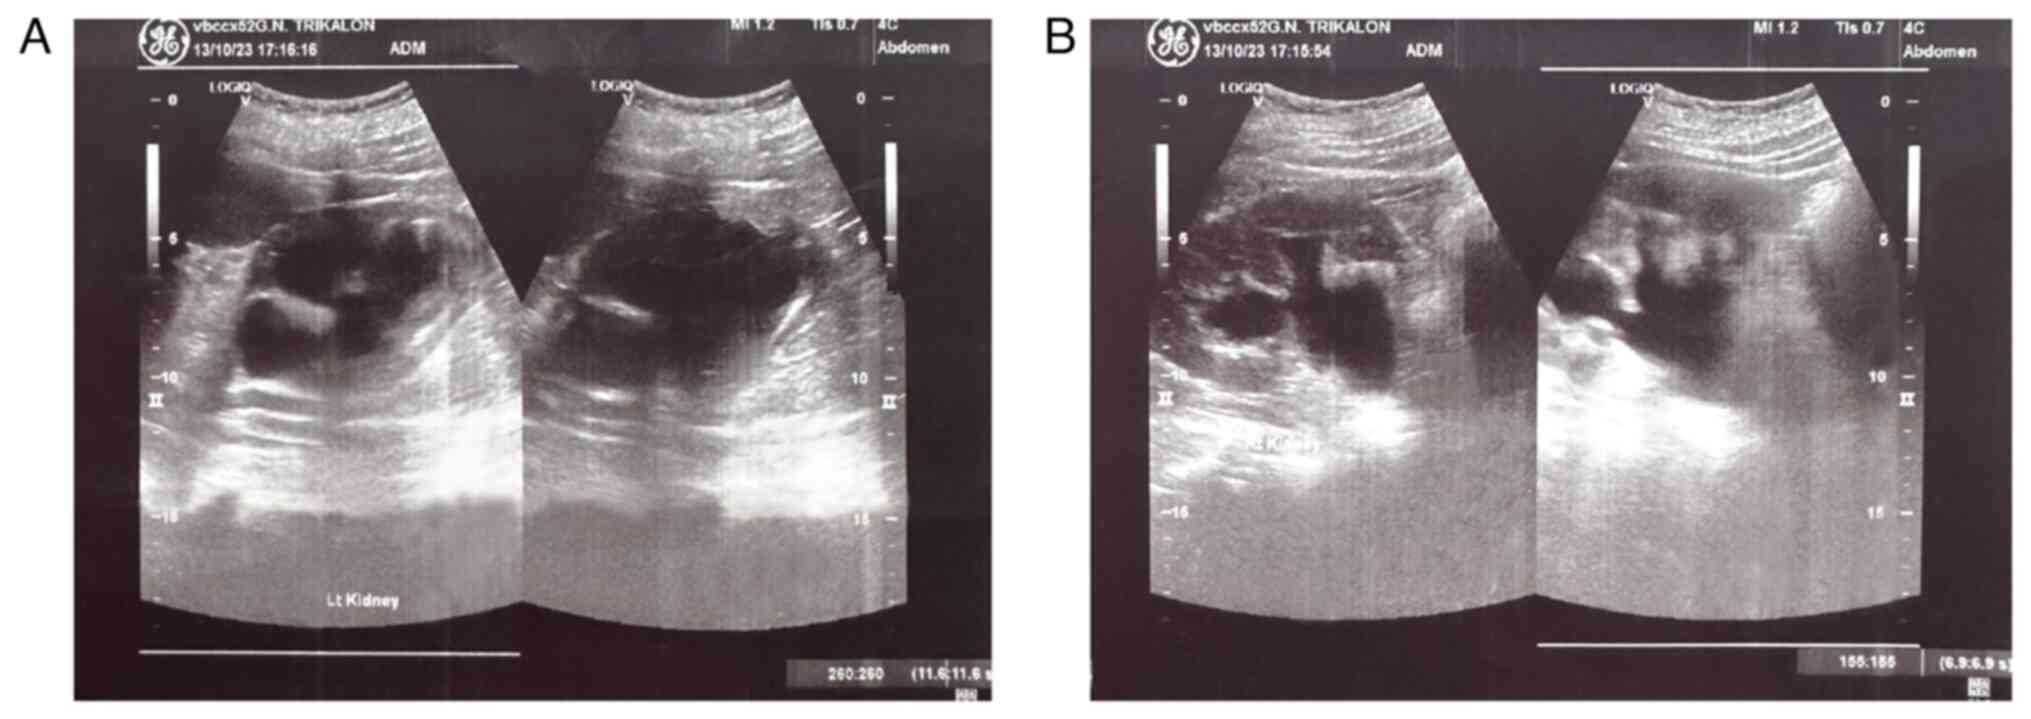

Figure 3

Preoperative ultrasound image of the kidneys revealing bilateral dilatation of the pelvicalyceal system and the upper ureters: (A) Right kidney, (B) left kidney.

Post-operative ultrasound image of the kidneys, which shows complete recovery of renal morphology and function: (A) Left kidney, (B) right kidney.

Upon a gynecological examination and upon the inspection of the vagina with a speculum, the cervix was not visible. In the upper third of the vagina, in the anatomical position of the cervix, a large solid mass was observed; the position of the external cervical os could not be clearly identified by visual inspection or palpation (Fig. 1). The transvaginal ultrasonographic findings were inconclusive. The scan detected the presence of a large well-circumscribed mass, with a maximum diameter of 10 cm, at the anatomical position of the cervix, raising suspicion of an intracervical leiomyoma (Fig. 2). A renal ultrasound revealed the bilateral dilatation of the pelvicalyceal system and the ipsilateral proximal ureter (Fig. 3). Furthermore, a computed tomography scan was performed, which revealed significant bladder dilatation and internal non-homogeneity of the cervical canal throughout its entire length, measuring 105x95x90 mm. This lesion caused the thinning of the external wall of the cervix and anterior displacement of the bladder. At the same time, it exerted compression on the posterior wall of the bladder, and malignancy arising from the cervix could not be excluded (Fig. 4). Additionally, computed tomography confirmed the dilatation of the pelvicalyceal system bilaterally up to the ureterovesical junction, accompanied by localized renal cortical thinning and lobulated contour of the left kidney. Magnetic resonance imaging was performed to further elucidate the findings of computed tomography. Magnetic resonance imaging revealed marked bladder distention with internal non-homogeneity of the cervical canal and the presence of a lobulated lesion that protruded intracanal with dimensions of 100x85x105 mm (Fig. 5). This finding was attributed to a large intracervical leiomyoma, strongly ruling out the possibility of cervical malignancy. The levels of tumor markers, namely carcinoembryonic antigen, cancer antigen 125, cancer antigen 15-3 and cancer antigen 19-9 were within the normal range.

Figure 7

Finally, the Alcian blue histochemical stain was used. Sections of 4 µm in thickness were dewaxed for 40 min at a temperature of 70˚C. The sections were placed in xylene for 10 min in room temperature. Subsequently, they were hydrated in decreasingly graded alcohols, submerged 10-15 times in each of the following solutions: 100% v/v ethanol, 96% v/v ethanol, 80% v/v ethanol and 70% v/v ethanol. Subsequently, the sections were washed using tap water and then distilled water, finally being ready for staining. A few drops of Alcian Blue stain [1% in 3% acetic acid (pH 2.5); Atom Scientific] were added and left there for 30 min. The sections were blotted and oxidized with 1% periodic acid solution for 10 min and then washed, firstly for 5 min using tap water and for 2 min using distilled water. Subsequently, Schiff reagent solution was added for 20 min; the section was washed with tap water for 5 min and rinsed with distilled water. Finally, Mayer's hematoxylin (Atom Scientific) was added for 5 min, and the section was washed in tap water for 5 min and rinsed in distilled water and finally, it underwent hydration in increasingly graded alcohols (same as before, in reverse), was mounted and coverslipped. The slides were studied under the same optical microscope (LEICA DM2000; magnification, x40, x100 and x400) as aforementioned. Alcian blue staining of the specimen ultimately revealed myxoid differentiation (images not available; data not shown). The immunohistochemical analysis, along with histological findings indicating no nuclear atypia, necrosis, mitoses, or invasive pattern, strongly suggested a diagnosis of leiomyoma with myxoid degeneration. These findings also supported the exclusion of other tumors, such as leiomyosarcoma. Macroscopically, an oval-shaped tumor with a maximum diameter of 10 cm exhibited a smooth outer surface entirely covered by serosa and the presence of a pedicle originating from the uterine isthmus was observed (Fig. 8). Following a smooth post-operative course and a distinct immediate improvement in renal function (Table I), the patient was discharged from the clinic on the 5th post-operative day. After 6 months, without the presence of ureteral stents, renal morphology and function had fully recovered (Fig. 9). The serum creatinine level was 1.1 mg/dl. The patient remains under regular follow-up evaluation at the Nephrology and Gynecology outpatient Department of the General Hospital of Trikala.